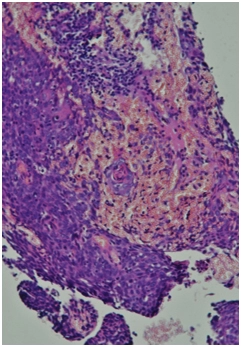

Гистологическое заключение. Высокодифференцированная плоскоклеточная карцинома с ороговением (G1) на всю толщину фрагментов.